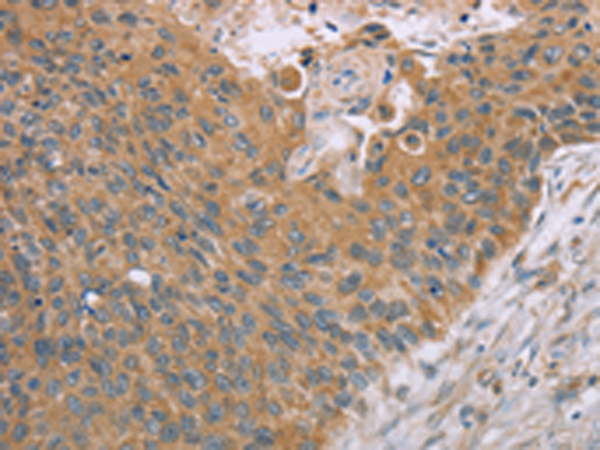

分类: 科研抗体货号: P12127别名: SMG; SMGA; SAMD4; SMAUG; SMAUG1应用: IHC反应种属: Human